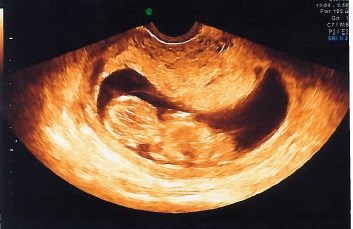

Baby-bølle ville ikke ligge i profil, men valgte at ligge med røven/ryggen til, og ville ikke rigtigt vende sig - på et tidspunkt svømmede den rundt og det så ud som om den ville være samarbejdsvillig, og der blev hurtigt taget et par billeder, som de vurderede nakkefolden ud fra. 1:7198, er da ret godt (jeg er 33 år) Hele seancen tog en god halv time, indtil vi måtte konstatere, at vi nok ikke fik bedre billeder en dem jeg har vedhæftet.

Det ene billede er hurtigt taget, mens bøllen lå på siden, det andet mens bøllen lå med røven/ryggen til